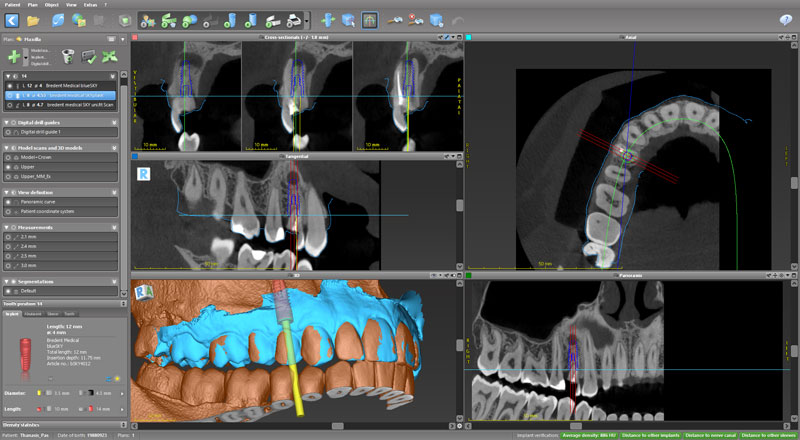

Ψηφιακό πλάνο θεραπείας

Κατευθυνόμενη τοποθέτηση εμφυτευμάτων

Σχεδιασμός χειρουργικού οδηγού

Πρακτική άσκηση: ο κάθε συμμετέχων θα σχεδιάσει σε ειδικό λογισμικό έναν χειρουργικό οδηγό

- Ψηφιακό πλάνο θεραπείας

- Κατευθυνόμενη τοποθέτηση εμφυτευμάτων

- Σχεδιασμός χειρουργικού οδηγού

- Πρακτική άσκηση: ο κάθε συμμετέχων θα σχεδιάσει σε ειδικό λογισμικό έναν χειρουργικό οδηγό